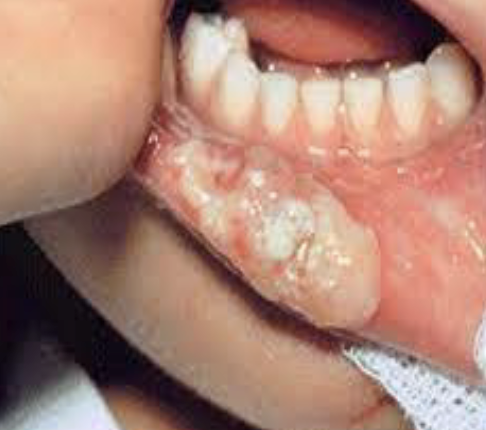

Complication – Pt develops an aphthous ulcer (canker sore) near site of local anesthetic deposition

Management – Soft tissue trauma from injection may instigate soft tissue pathologies such as aphthous ulcers and herpetic lesions if your pt is prone to them. Management of soft tissue ulcers is usually managing the symptoms with warm salt water, topical ointment, etc

Prevention: Aphthous Ulcer Formation

There is nothing that can be done to prevent this from happening, however if your pt is known to be prone to aphthous ulcer or herpetic lesion formation, warning them beforehand would be prudent